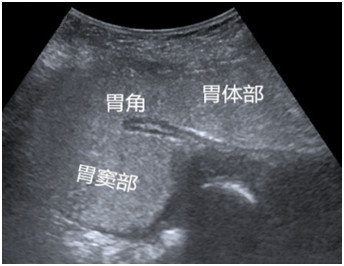

胃肠超声造影检查是采用口服造影剂充盈胃、肠腔,通过改善胃肠的超声内部环境,以利于超声波声束穿透,使胃肠结构和其病变在超声检查下更加清晰地显示,同时通过动态观察对胃肠功能作出有效评估。它是一种无创、无射线、不插管、无痛苦、安全、简便有效、可重复性强的检查方法。

目前,超声造影检查在胃肠疾病方面虽有其局限性,但作为一种简便、无创、准确性较高的客观影像学检查方法,它弥补了其他检查方法的一些不足和缺陷,适用于胃肠道疾病的筛查,尤其适用于胃肠镜禁忌症的患者。